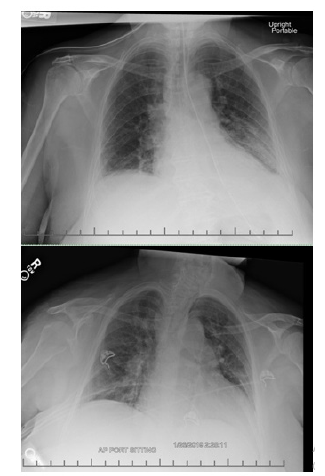

Electrocardiogram revealed possible left atrial enlargement and left ventricular hypertrophy, indicative of progressive left ventricular failure. Her electrocardiogram also showed anterolateral T-wave inversion (Figure 1). On telemetry, she had a normal sinus rhythm with a ventricular rate of 69. Transthoracic echocardiography revealed an estimated left ventricular ejection fraction of 25%. Additional findings include grade III diastolic dysfunction with elevated left atrial pressure, severe left atrial enlargement with severely abnormal left atrial ventricular index, severe right ventricular enlargement with normal function, right ventricular base measuring 5.6 cm, severely enlarged right atrium, severe mitral regurgitation, mitral regurgitation grade severity of 0.5 cm2, moderate to severe tricuspid regurgitation, and her inferior vena cava barely collapsed during inspiration suggesting elevated right atrial and ventricular end-diastolic pressures (Figure 2) Chest x-ray (Figure 3) revealed a nonspecific right infrahilar opacity suggestive of atelectasis or an infiltrative process, in addition to mild-to-moderate cardiomegaly.

Imaging

Routine imaging for methamphetamine associated cardiomyopathy includes chest x-ray and 2dimensional echocardiography. We performed a trans-thoracic echocardiogram at baseline to test for left ventricular ejection fraction (LVEF) and chamber dilatation. We define the diagnosis of cardiomyopathy as LVEF less than 40% per the American Society of Echocardiography, with methamphetamine abusers having more severe dilatation and systolic dysfunction. Many reported cases also have thrombotic complications on echocardiogram [10]. Additional testing may include cardiac magnetic resonance imaging (CMR) with late gadolinium enhancement (LGE) which can identify regional fibrosis, predictive of irreversible MACinduced damage [11]. Fibrotic changes from methamphetamine abuse suggest a longer duration and increased severity of drug use over time [12].